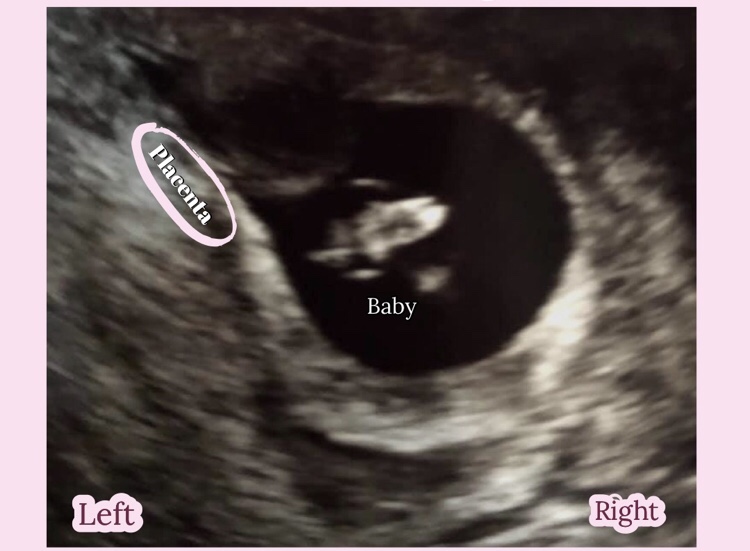

Gender pros predicted girl with Ramzi theory. Anyone agree?

Girl 💗

Abdominal or vaginal

@winelvr8, my baby now was on the left abdominal at 10 weeks so when I find out gender I’ll let you know